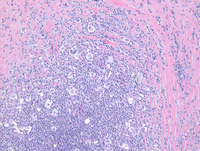

CD20 and PAX5 downregulation in cHL

CD20 immunostain (bottom left) demonstrates scattered small B cells staining positive for CD20 while the Hodgkin cells are negative for CD20, consistent with down regulation of germinal center and B-cell program in the cells.

Likewise, PAX5 (bottom right) demonstrates strong nuclear positivity in the surrounding B cells while the clusters of the Hodgkin cells in the center of the field demonstrate weak PAX5 expression consistent with the down-regulation of germinal center and B-cell program in these cells.